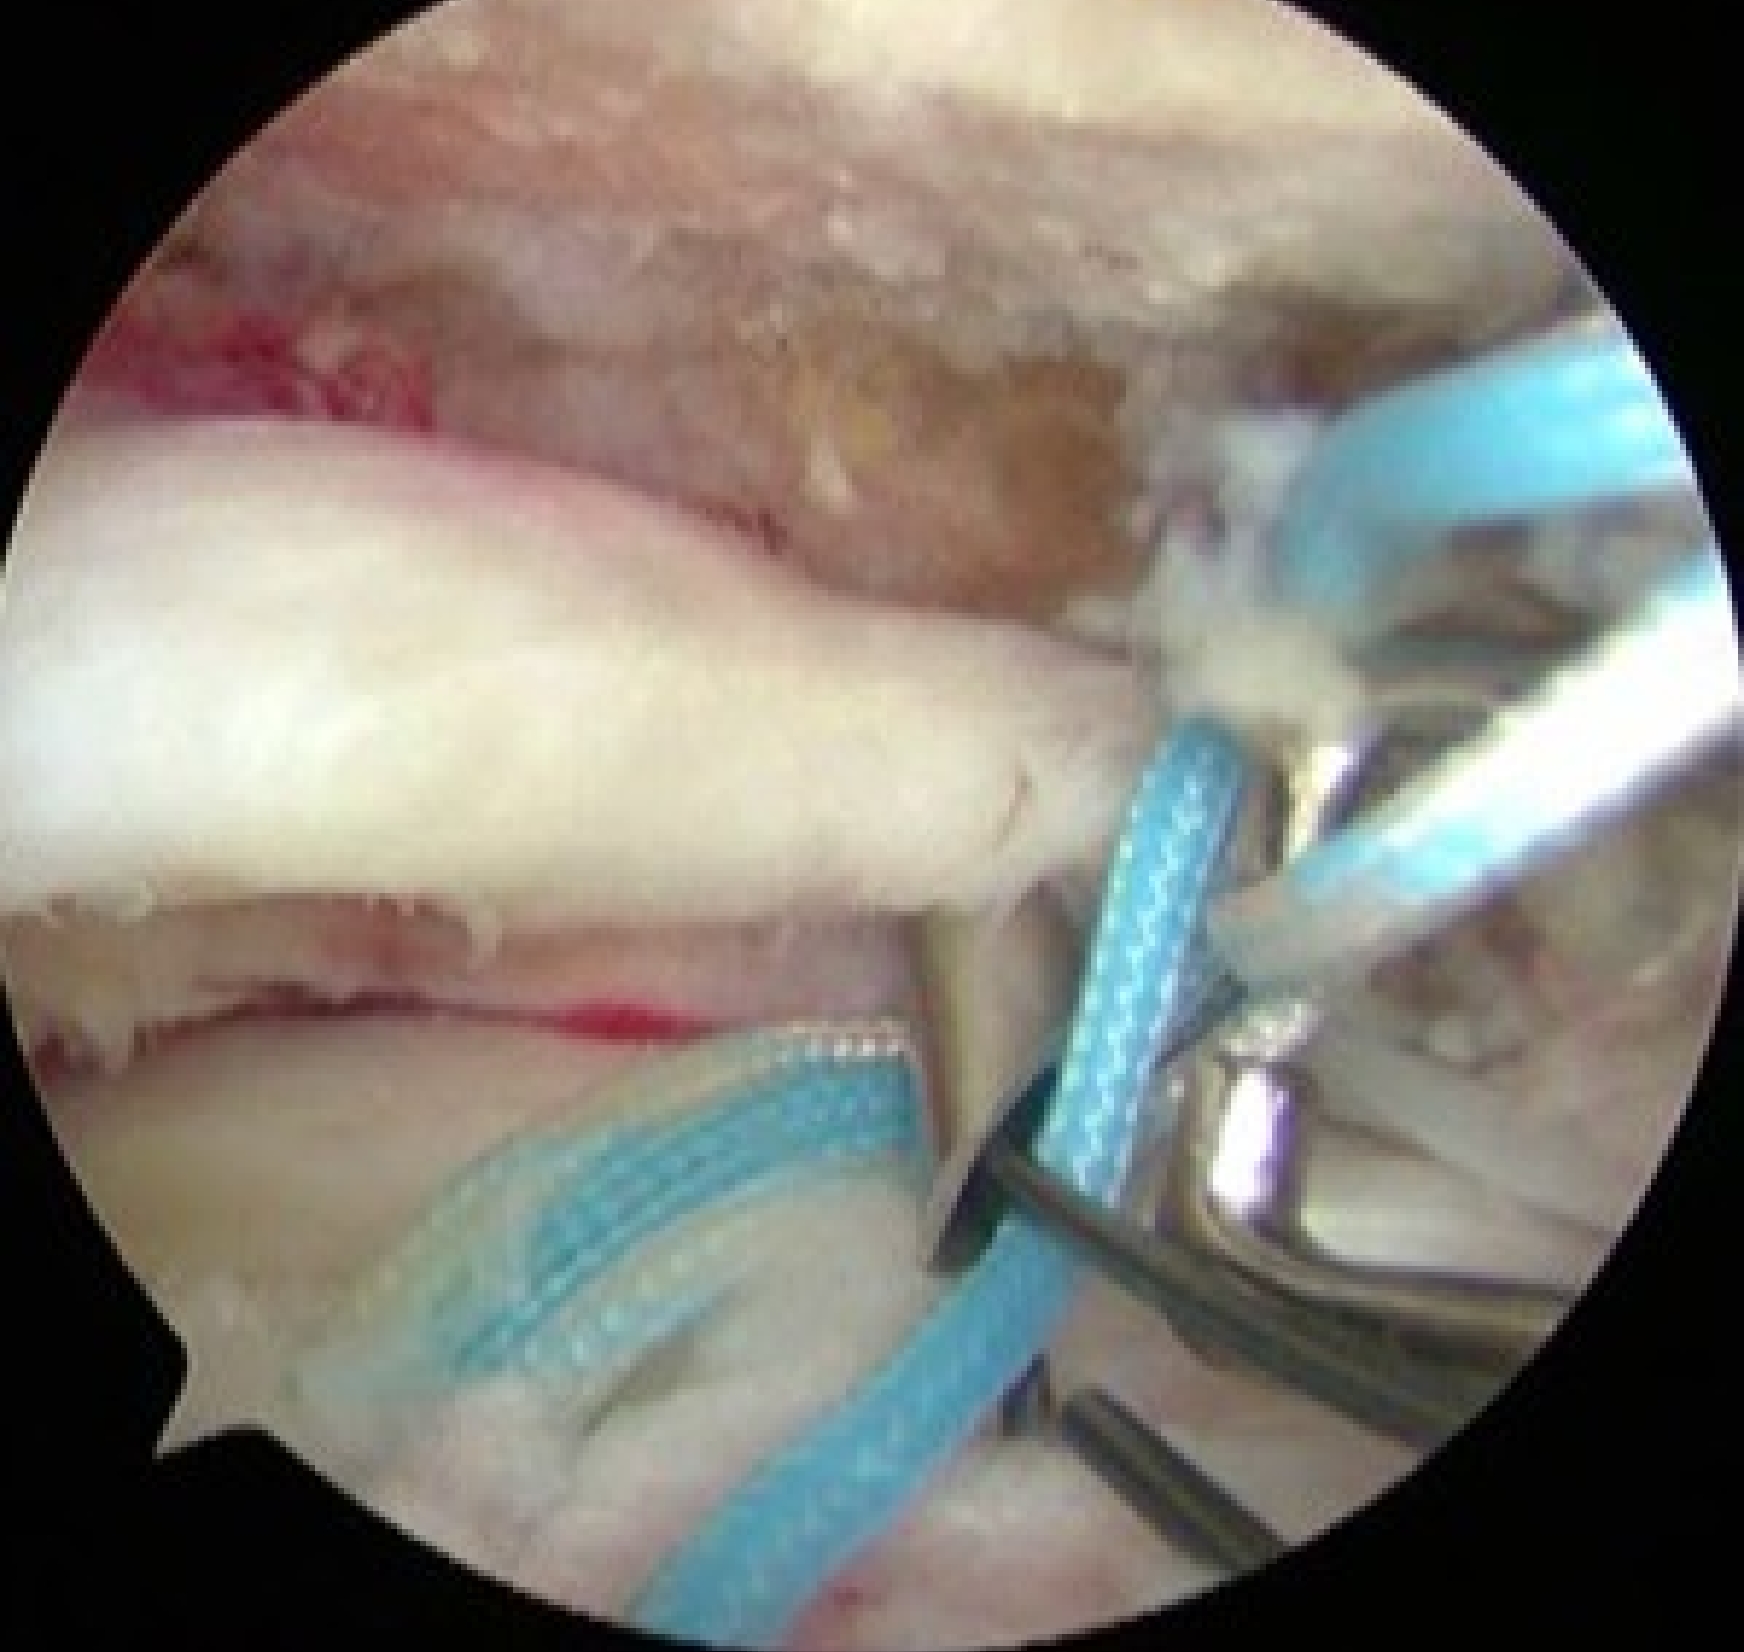

Suture-bridge完成

露出していた骨頭は見えなくなり、腱板で覆われています。